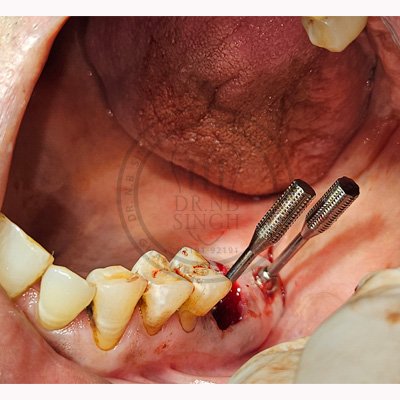

Case – 11 Baleram